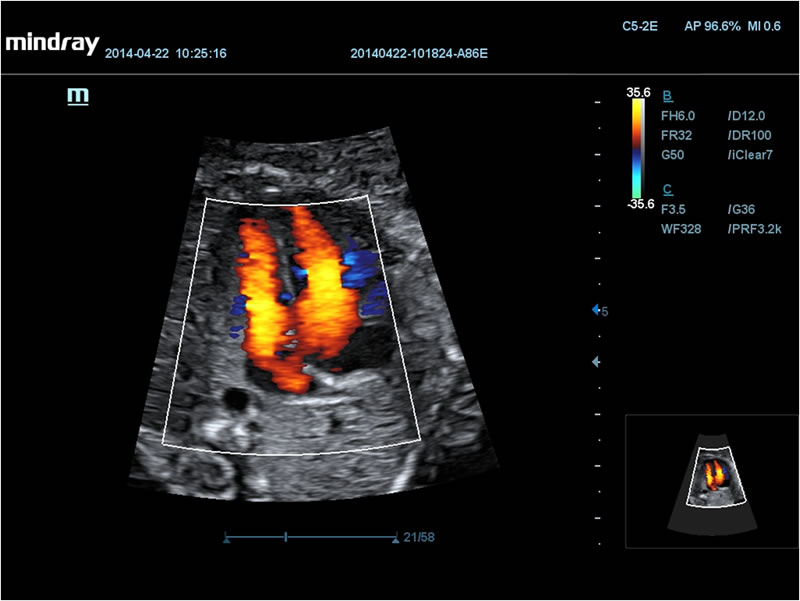

Пупочные артерии